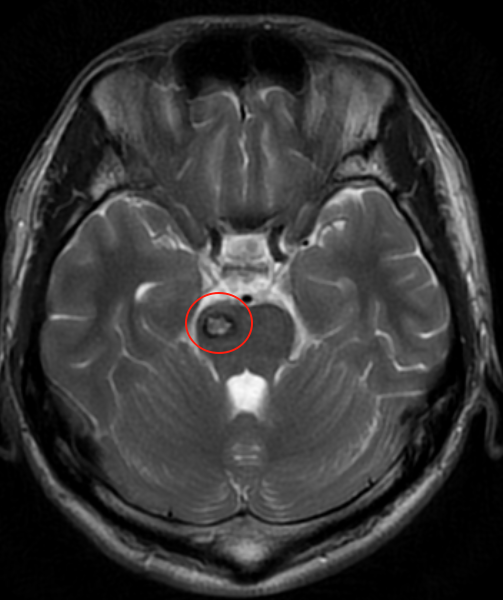

19歲少年飛宇,一個40×25×31mm的巨大腫瘤已完全占據(jù)第三腦室,從室間孔向下壓迫中腦。三腦室,這個前后僅2.5-3cm、寬約0.5cm的狹小腔隙,卻密集分布著維系生命的關鍵結構。

一個40×25×31mm的巨大腫瘤已完全占據(jù)第三腦室,從室間孔向下壓迫中腦。

• 2. 脈絡膜裂是位于穹窿和丘腦之間、脈絡叢附著處的一條潛在的裂隙。巨大腫瘤導致其扭曲、粘連、被擠壓變薄。安全有效地打開此裂隙而不損傷下方的深部靜脈系統(tǒng)和丘腦至關重要,操作需在極其有限的深部空間內精細進行。分離不當易撕裂脈絡膜或損傷其下方的靜脈系統(tǒng)(如丘紋靜脈),導致災難性出血或靜脈性梗死。

• 3. 巨大腫瘤本身有豐富血供,深部止血困難,大量出血迅速充滿術野,干擾操作并增加損傷風險。而飛宇的腫瘤質地堅韌似橡皮膏,與三腦室壁、丘腦、深部血管黏連緊密,只能分塊切除或借助CUSA,強行牽拉易導致出血或傷及周圍結構。